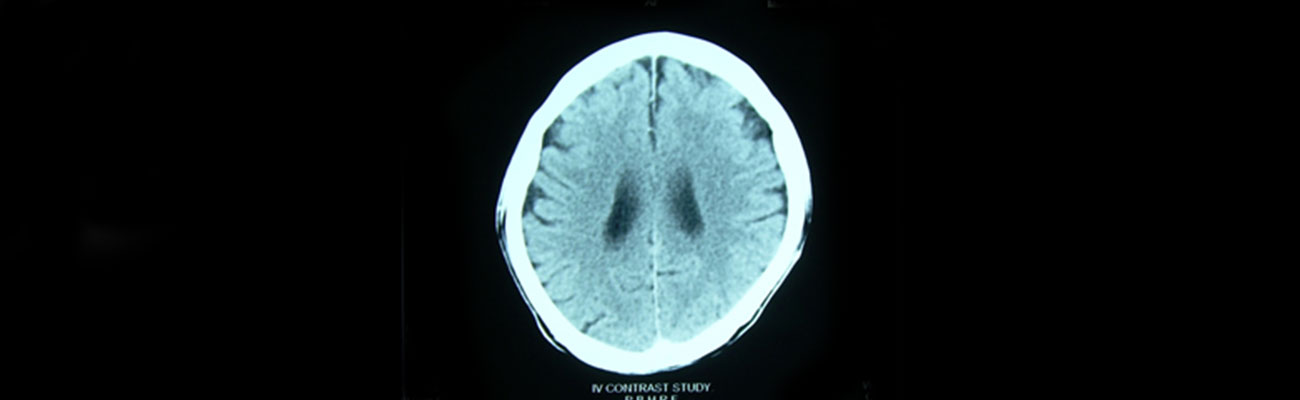

As per his initial observations, C.T.Scan of Brain done on 24.09.2003 shows "…Rounded isodense well outlined lesion at subcortical area of parietal lobe with marked perilesional edema showing compression on right lateral ventricle & right sylvian fissure- meningioma".

Gradually all his clinical symptoms has gone within two years of our medication, at present he has no pain in left side & no headache is there with gradual improvement of left sided weakness and left facial palsy. During his treatment Follow up C.T. Scan of Brain (Plain & Contrast Study) done on dated 06.09.2005 shows ….. " Normal CT scan of brain."